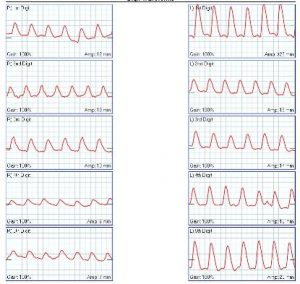

A Common concern for patients who have purple feet is whether they have poor circulation. And by the term ‘circulation’ they mean artery flow. This is actually uncommon. For arterial blockages to cause color changes, they need to be severe. But in reality, most patients will not have critical limb ischemia. In fact, color changes are much more typical of constricted arteries or of blood pooling in dilated arteries. But still, sometimes ruling our artery blockages makes sense (or you just do it to address the patient’s anxiety). If that is the case, the first screening test will be the ankle brachial index. More comprehensive information is available with pulse volume recordings. Both of these tests will be able to show if there is reduced artery blood flow to the feet. They will usually not be enough to show where the blockage is or if fixing it is possible. But they are good for screening purposes.

Even more information can be obtained with the toe brachial index and with toe-wave tracings. These are also known as photoplathysmographic tracings or PPG’s. The PPG’s can be repeated at room temperatures and with heating or cooling. If there is change you can diagnose artery constriction with temperature. This may lead to a diagnosis of acrocyanosis, Raynaud’s or similar condition. If the waveforms are abnormal, but do not respond to temperature changes, you should look for specific reasons. Practically, you can order pulse volume recordings and toe waveform tracings at the same time.